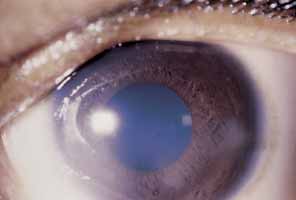

IRIS AND UVEA. HZO can cause either a nongranulomatous or granulomatous iridocyclitis (anterior

cells and protein flare.62 A severe “plastic” iridocyclitis, with hypopyon, hyphema, and

intractable secondary glaucoma, can be observed (Fig. 16). As a result of chronic iridocyclitis, corneal edema secondary to

endothelial damage and sectoral iris atrophy can occur.62 Endothelial cell loss is especially common with herpes zoster keratouveitis, even

with normal intraocular pressure.64,65 Histopathologically, herpes zoster iritis is an ischemic, occlusive vasculitis. The

typical sector iris atrophy that accompanies HZO is the

result of focal ischemic necrosis (Fig. 17).70 In contrast, herpes simplex iritis is primarily a lymphocytic infiltration

without ischemia, and causes a more diffuse iris atrophy.16,72,73  Fig. 16 Herpes zoster ophthalmicus. Corneal edema, abscess formation, and hypopyon

iridocyclitis in an eye that was subsequently enucleated for intractable

glaucoma and pain. Fig. 16 Herpes zoster ophthalmicus. Corneal edema, abscess formation, and hypopyon

iridocyclitis in an eye that was subsequently enucleated for intractable

glaucoma and pain.

|

Fig. 17 Sectoral iris atrophy, status post–herpes zoster ophthalmicus. Note

the moth-eaten appearance of iris in sectoral area, underlying

a corresponding area of sclerokeratitis and limbal vascularization. Fig. 17 Sectoral iris atrophy, status post–herpes zoster ophthalmicus. Note

the moth-eaten appearance of iris in sectoral area, underlying

a corresponding area of sclerokeratitis and limbal vascularization.

|